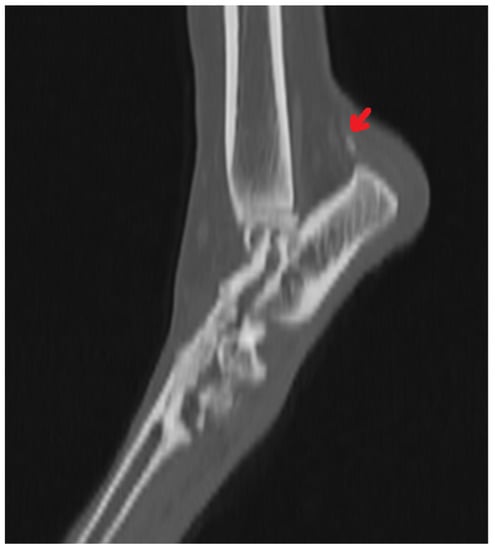

Radiography can be used for the indirect imaging of Achilles tendon injuries, but its usefulness is limited due to the superimposition of bones and poor contrast, as well as the structure visibility of soft tissues [1,40]. Radiographs can only show the foci of tendon mineralization and the swelling of adjacent soft tissue (Figure 1) [40,43]. Computed tomography (CT) is a cross-sectional imaging modality and has improved the identification of pathological lesions of the calcaneal tendon, such as enthesopathies and tendinopathies. CT provides sectional images; therefore, it eliminates the problems of superimposition correlated with conventional radiology. Achilles enthesopathy is defined as abnormality of the tendons and their attachment to the calcaneal tuber (Figure 2 and Figure 3).

Figure 2. CT image of the mineralization of the Achilles tendon (arrow).

Figure 3. CT 3D image reconstruction of the mineralization of the Achilles tendon (arrow).